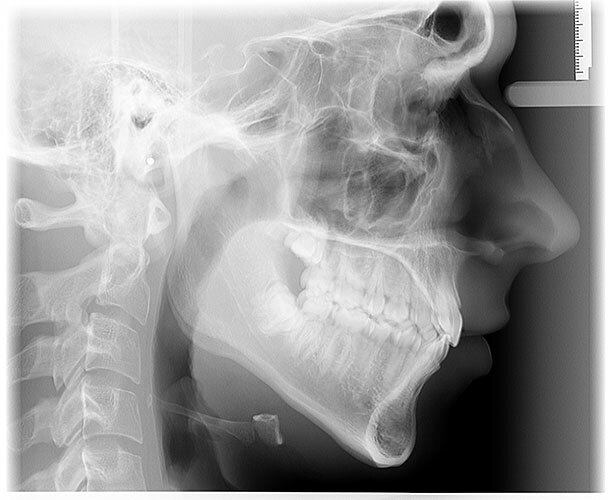

Dexis OP 3D Pro donosi potpuno digitalno rešenje za ortopantomogram (OPG), telediogram, skanogram, bitewing, i 3D snimke vilice, čime pruža sveobuhvatnu podršku dijagnostici za različite stomatološke zahvate i analize.

Bilo da vam je potrebno jednostavno snimanje zuba ili složeniji pregled maksilarnih sinusa i TM zglobova, naš centar je tu za vas.